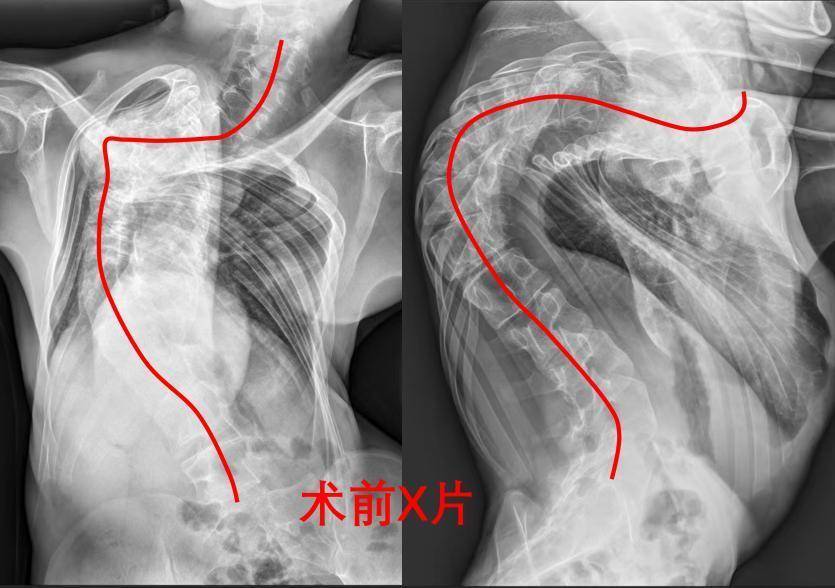

“孩子从小体弱,莫得母爱,再难皆要给他治。”小王的病成了他父亲的心结,16年来,带他先后赶赴江西、上海、北京等地求医,但皆无果。经病友先容,小王慕名找到重医附二院骨科二病区脊柱乖张团队。齐集影像学门径与临床评估,团队明确:重度脊柱侧弯,脊柱侧弯角度(Cobb角)约140度,严重胸廓乖张,肺功能不全,为了保证安全,提高疗效,给小王制定头盆环牵引术、脊柱后路松解术、脊柱后路矫形术的分期休养决策。

“脊柱后路截骨矫形植骨和会椎弓螺钉内固定术,是处置脊柱乖张最透顶的决策,但难度大、风险高。”赵登副主任医师说,患者脊柱侧弯角度大,椎体发育结构格外,不仅椎弓根螺钉植入难度大,术中稍失慎触碰脊髓或大血管,将导致瘫痪、大出血等致命风险。

流程近1年的牵引、松解、再牵引等休养,小王的脊柱乖张较着变小了,呼吸功能获得了很好的改善,为安全地执行脊柱矫形手术打下了坚实的基础。告诫丰富的团队进行了严实的术前指标,作念了万无一失的决策。但小王竟因缅念念用度问题产生不念念手术的念头。“你此时若撤消,难谈不念念达成东谈主生价值了吗?”为之动容的楚磊主任宽慰谈,而况团队从看成上处置了小王的黄雀伺蝉。